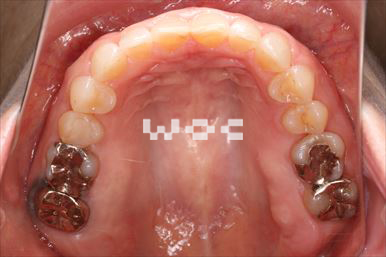

八重歯・叢生舌側矯正

上下舌側矯正を希望。奥歯を後方へ移動し、非抜歯で治療を終わることができました。

- 年齢:17歳女性

- 主訴:前歯が斜めになっている

- 基本矯正料金:1,250,000円

- 治療期間:1年7ヶ月

- 非抜歯